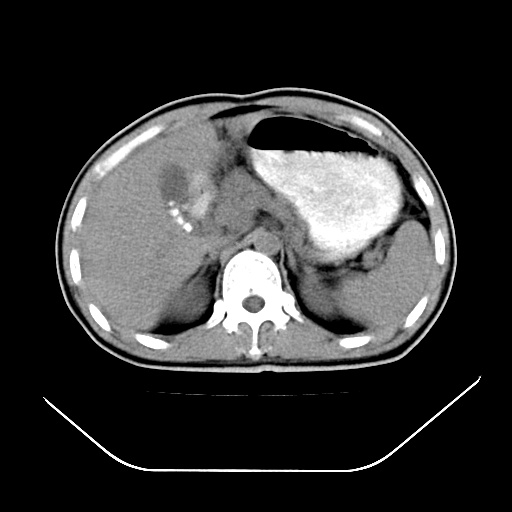

以下是引用深泽交通医院在2008-7-17 12:05:00的发言:[br]肝门淋巴结肿大;胆结石

以下是引用随光逐影在2008-7-17 17:52:00的发言:[br]1)胆囊结石。2)肝门及胰头区淋巴结肿大可能(原因不明);建议行进一步检查。

以下是引用卜一在2008-7-17 16:37:00的发言:[br]支持胆囊结石!!!至于胰头区病变——建议强化后再定论!